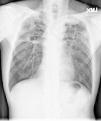

A 59-year-old man with no medical history presented with productive cough and hemoptysis for two months. Low-grade fever, fatigue and body weight loss were noted. Physical examination disclosed crackles in both lungs and cachectic appearance. Blood examination revealed hypoalbuminemia and generalized inflammation with a high C-reactive protein level. Chest radiography and computed tomography showed multiple cavities of various sizes and segmental consolidations in both lungs with upper lobes predominance (Fig. 1A and B). He was admitted under the impression of pulmonary tuberculosis initially. Sputum acid-fast stain and tuberculosis culture did not yield tuberculosis bacilli. Sputum culture yielded Aspergillus fumigatus later and ultrasound-guided fine-needle aspiration of a pulmonary nodule showed hyphae consistent with Aspergillus spp. Chronic pulmonary cavitary aspergillosis was diagnosed. Serial survey did not show evidence of immunodeficiency. After a 6-month course of voriconazole therapy, both symptoms and images remarkably improved (Fig. 2) and body weight increased. Longer duration of antifungal therapy is indicated.

Aspergillosis is an illness caused by aspergillus organisms with various manifestations. Chronic cavitary pulmonary aspergillosis is a multicavitary disease in immunocompetent patients and progresses over time. Previous mycobacterium infections, allergic bronchopulmonary aspergillosis and chronic obstructive pulmonary disease are the most common predisposing conditions.1 Most patients are often suspected of having tuberculosis initially. The common symptoms include cough, shortness of breath, hemoptysis and body weight loss. Radiographic examination usually disclosed multiple cavities of various sizes and ill-defined regions of consolidation, mainly in upper lungs. Diagnosis can be made by classical clinical and radiographic presentations combined with a positive aspergillus serology and/or culture of Aspergillus spp. from the lungs.2 Antifungal agents are the mainstays of therapy. Lifelong therapy is often required.3,4